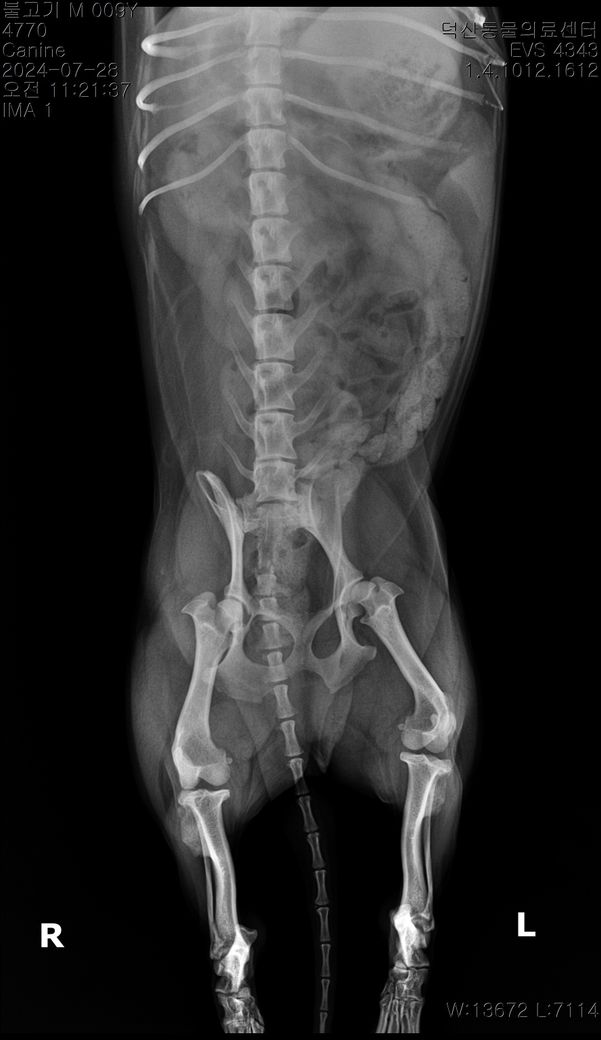

순차적으로 고관절 에 관해 봐주시기 부탁드립니다.

3 사진이 순차적입니다 순차적으로 고관절에 큰 변화가 있나요?

마지막 보여지는 부분에서 오른쪽 고관절이 탈구된거라고 하는데 이전 사진에서는 탈구가 안되었나요?

마지막 사진은 촬영할때 환자가 몸을 꼬아서 뒤틀려진 고관절이 찍힌 사진으로 이 사진으로는 고관절 탈구를 평가하면 안됩니다. 앞 사진에서는 탈구가 관찰되지 않고, 특히 연골이형성품종에 해당하는 환자이기 때문에 정상범주가 매우 높습니다. 주치의의 상담을 받으시기 바랍니다.